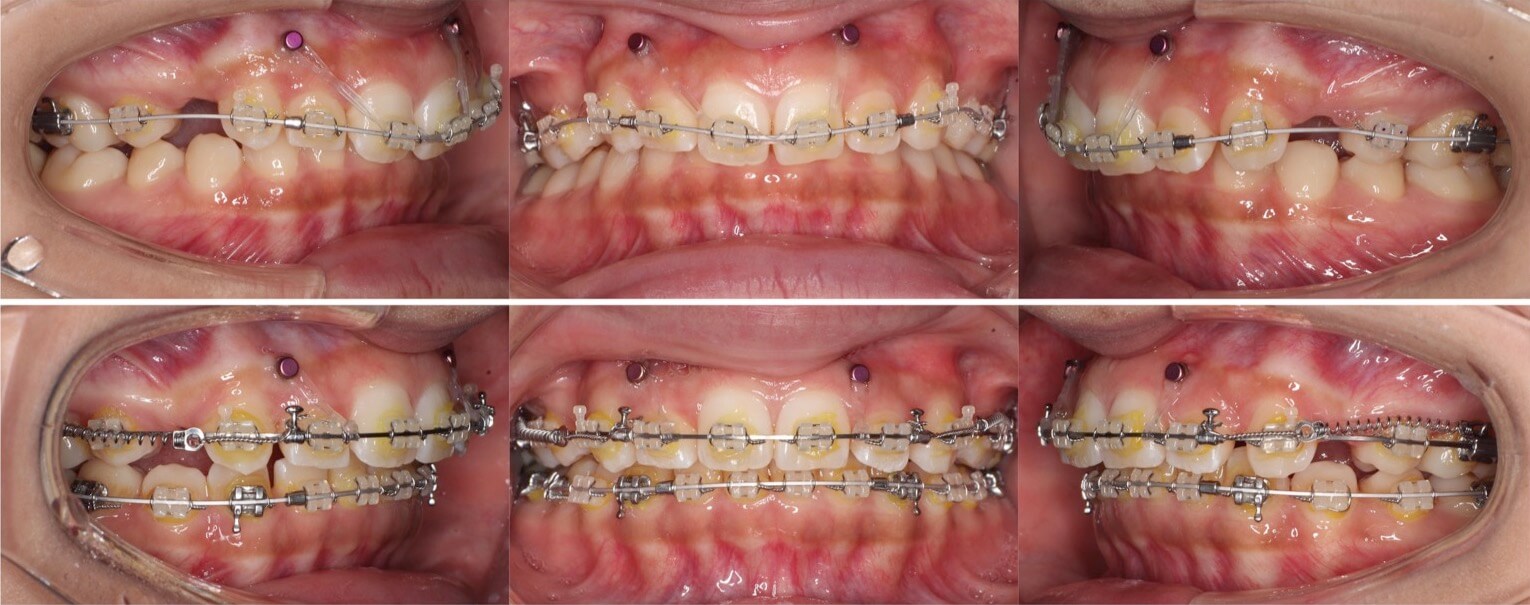

大学生男性・唇側矯正装置・4本抜歯

口元の突出もある重度の過蓋咬合症例は、表側矯正装置の方が確実に治療が可能です。このようなケースの治療期間は3年を超えてしまいます。側方のシザースバイトも併発しているため、下の歯並びにブラケット装置を装着する面積を確保する事に苦戦しました。治療途中は何回もワイヤーが上の歯で噛み切ってしまい折れてしまうため、複雑なワイヤーを併用する事で過蓋咬合を改善しました。

<症例概要>

主訴:口元の突出

年齢・性別:大学生男性

住まい:千葉県八千代市

症状:過蓋咬合・上下顎前突・左側シザースバイト

治療方針:抜歯空隙の閉鎖(最大固定)

治療装置:唇側矯正装置

固定装置:歯科矯正用アンカースクリュー(上頬側x2)

抜歯:上下左右4番(計4本)

治療期間:3年2か月

リテーナー:下フィックスタイプ+上下プレートタイプ

治療費用:968,000(税込)

代表的副作用:痛み・治療後の後戻り・歯根吸収・歯髄壊死・歯肉退縮

▶︎その他の副作用